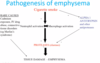

Recall the pathophysiology of emphysema

Smoking causes inflammation

Neutrophil and macrophage involvement

Proteases recruited

Breakdown of epithelium

How might histology differ in emphysema caused by smoking vs A1-AT deficiency?